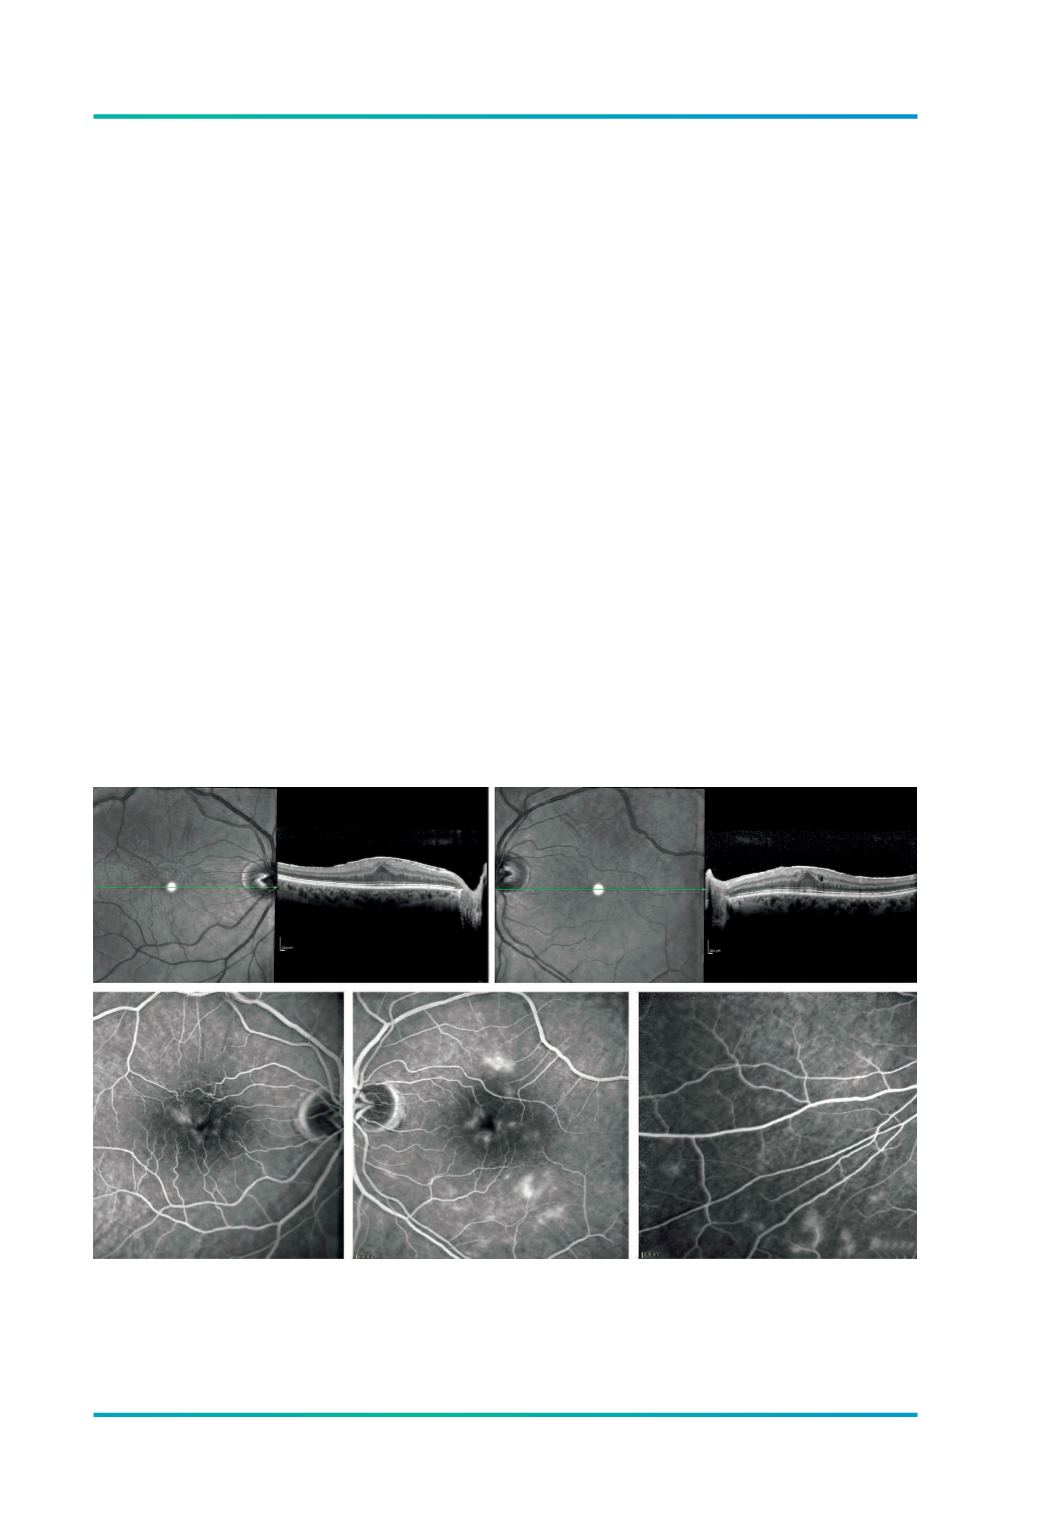

Figura 1.

Paciente com hipovisão progressiva, com 6/10 em OD e OE. Havia sido proposto para remoção cirúrgica da

MER baseada apenas nas imagens de OCT (A e B). A avaliação complementar com angiografia (C, D e E)

demonstrou uma vasculite incipiente de pequenos vasos, não detectável fundoscopicamente, revelando-se

secundária a infecção por tuberculose, melhorando da vasculite apenas com tratamento anti-tuberculoso.

A

B

C

D

E